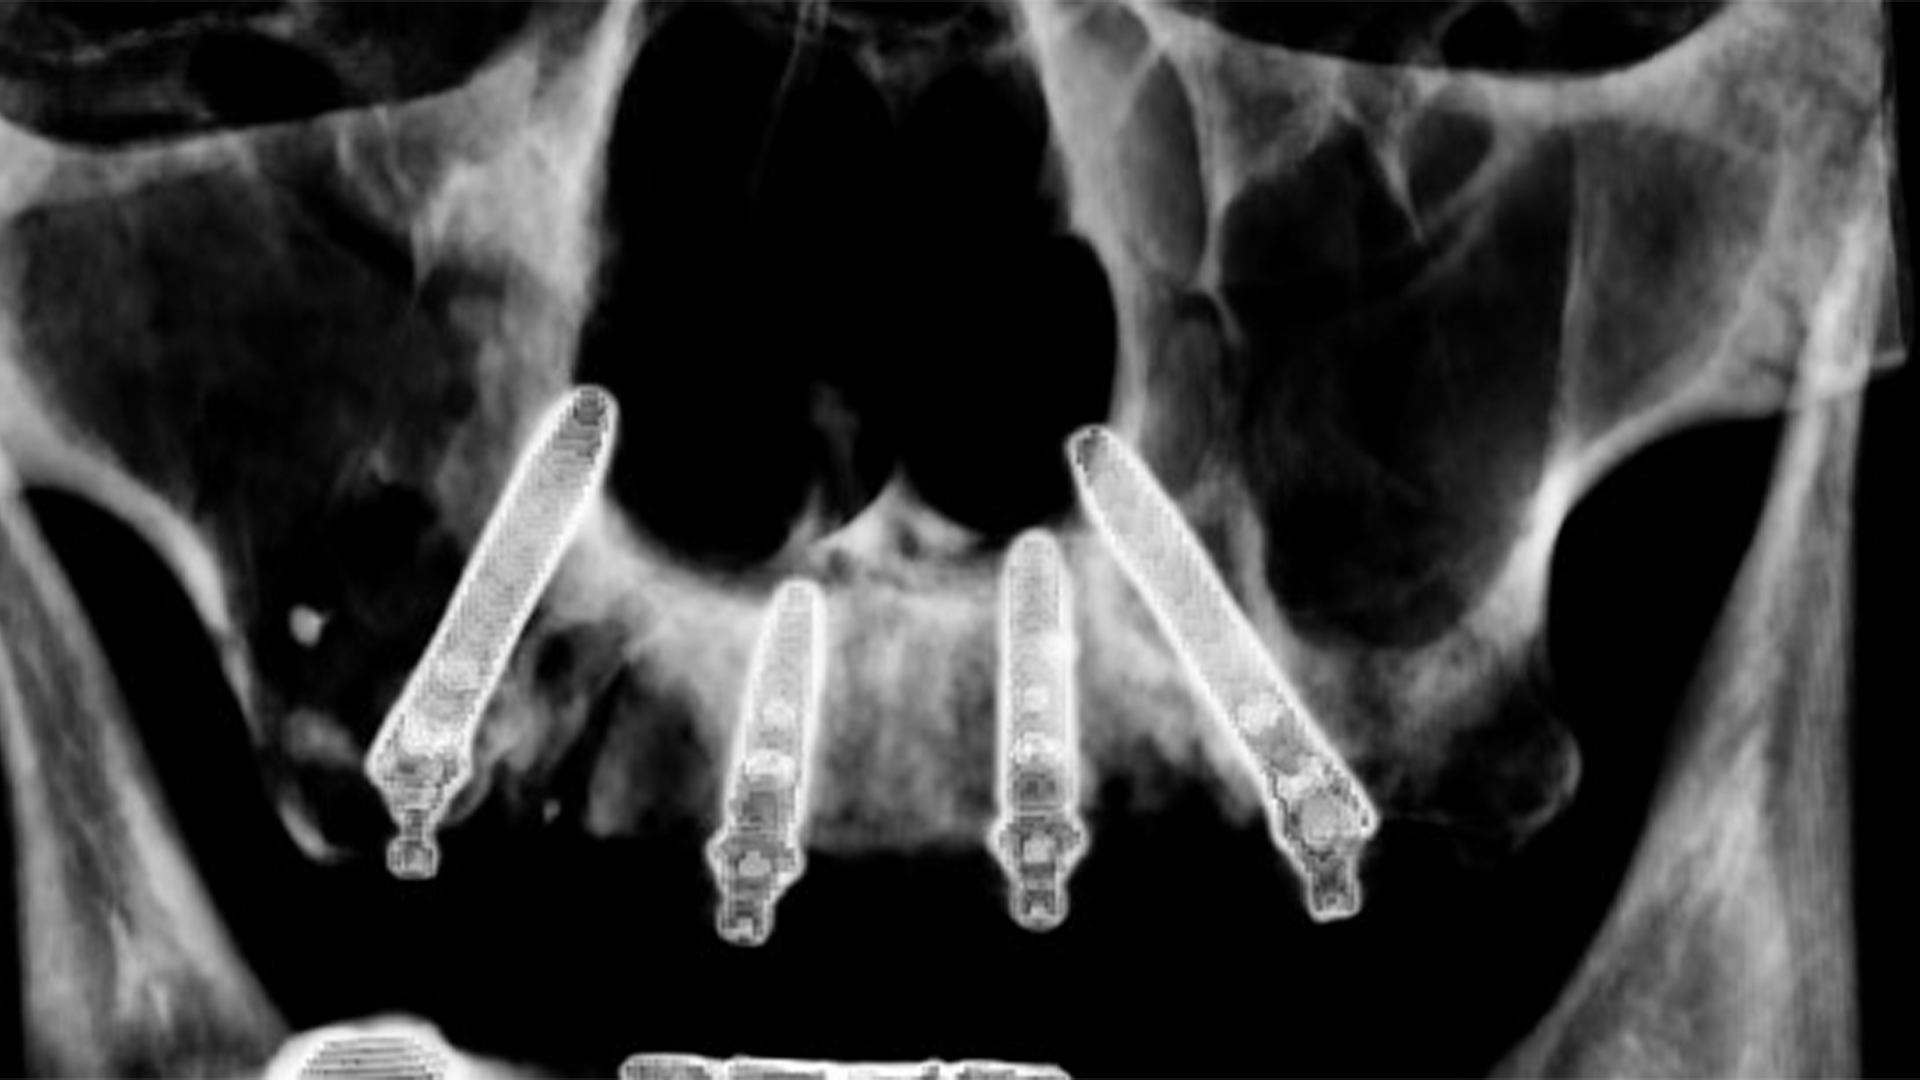

tac dopo